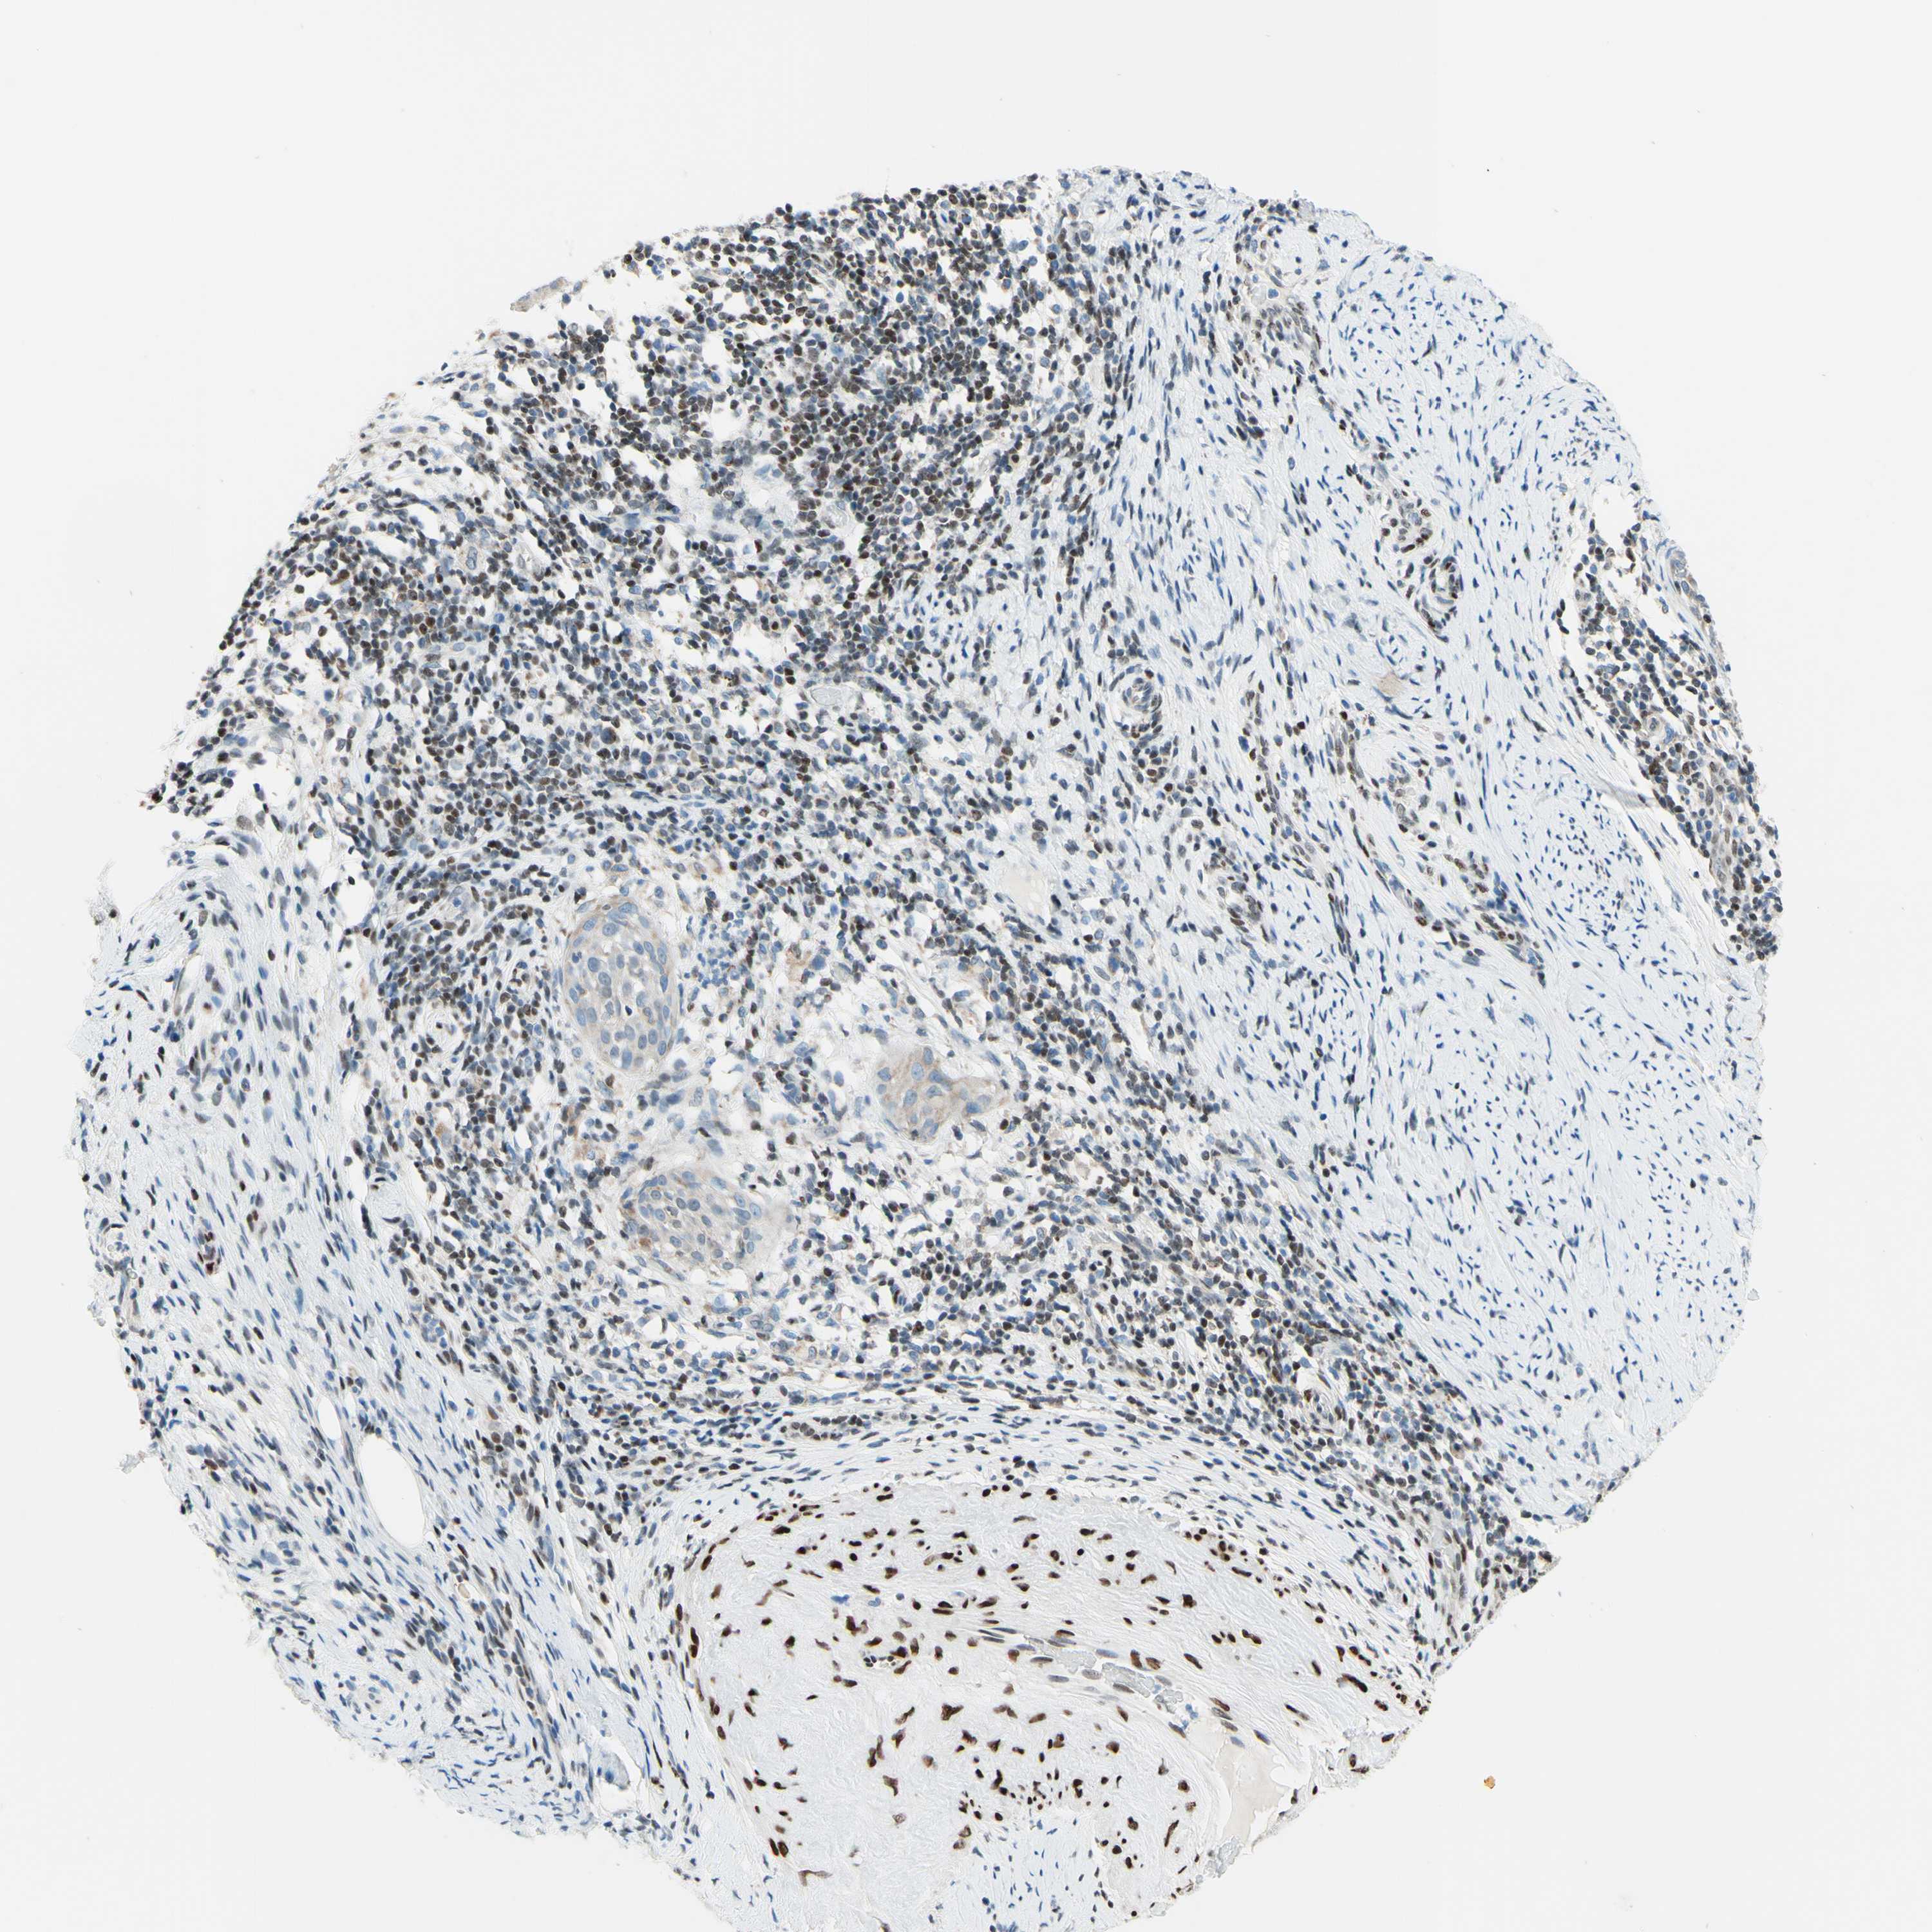

CERVICAL CANCER - Protein expressioni

A mouse-over function shows sample information and annotation data. Click on an image to view it in a full screen mode. Samples can be filtered based on level of antibody staining by selecting one or several of the following categories: high, medium, low and not detected. The assay and annotation is described here.

Note that samples used for immunohistochemistry by the Human Protein Atlas do not correspond to samples in the TCGA dataset.

Antibody stainingi

Antibody staining in the annotated cell types in the current human tissue is reported as not detected, low, medium, or high, based on conventional immunohistochemistry profiling in selected tissues. This score is based on the combination of the staining intensity and fraction of stained cells.

Each image is clickable and will lead to virtual microscopy that enables deeper exploration of all samples and also displays staining intensity scores, fraction scores and subcellular localization as well as patient and tissue information for each sample.

Antibody HPA048677

Antibody HPA056480

Antibody CAB011574

Staining

High

Medium

Low

Not detected

Intensity

Strong

Moderate

Weak

Negative

Quantity

>75%

75%-25%

<25%

None

Location

Nuclear

Cytoplasmic/membranous

Cytoplasmic/membranous,nuclear

Squamous cell carcinoma, NOS

Adenocarcinoma, NOS